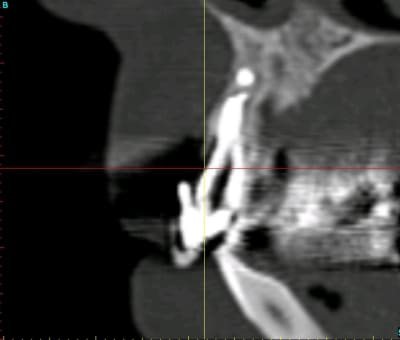

Voilà ce que l'on arrive à faire mais ce fut limite!

Interactive dx8dv8 - Eugenol